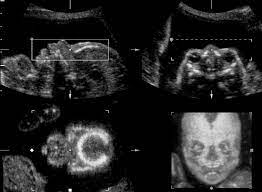

Ultrasound Images Of A Normal Fetus A And A Fetus With Trisomy 21 B Download Scientific Diagram

Down syndrome is a genetic disorder caused when abnormal cell division results in an extra full or partial copy of chromosome 21. This test is done between 15 and 20 weeks of pregnancy. In 2011 a nicely done experiment by Marshall et al showed that regular hamstring stretching substantially increased range of motion in normal university kids95 Specifically after a 4-week stretching program consisting of 4 hamstring and hip stretches performed 5 times per week their range increased about 16 or 20. Down syndrome is a genetic disorder caused when abnormal cell division results in an extra full or partial copy of chromosome 21. In Down syndrome the nuchal translucency measurement is abnormally large as shown on the left in the ultrasound image of an 11-week fetus. How is a dating scan performed. The 20-Week Anatomy Scan May 2017.